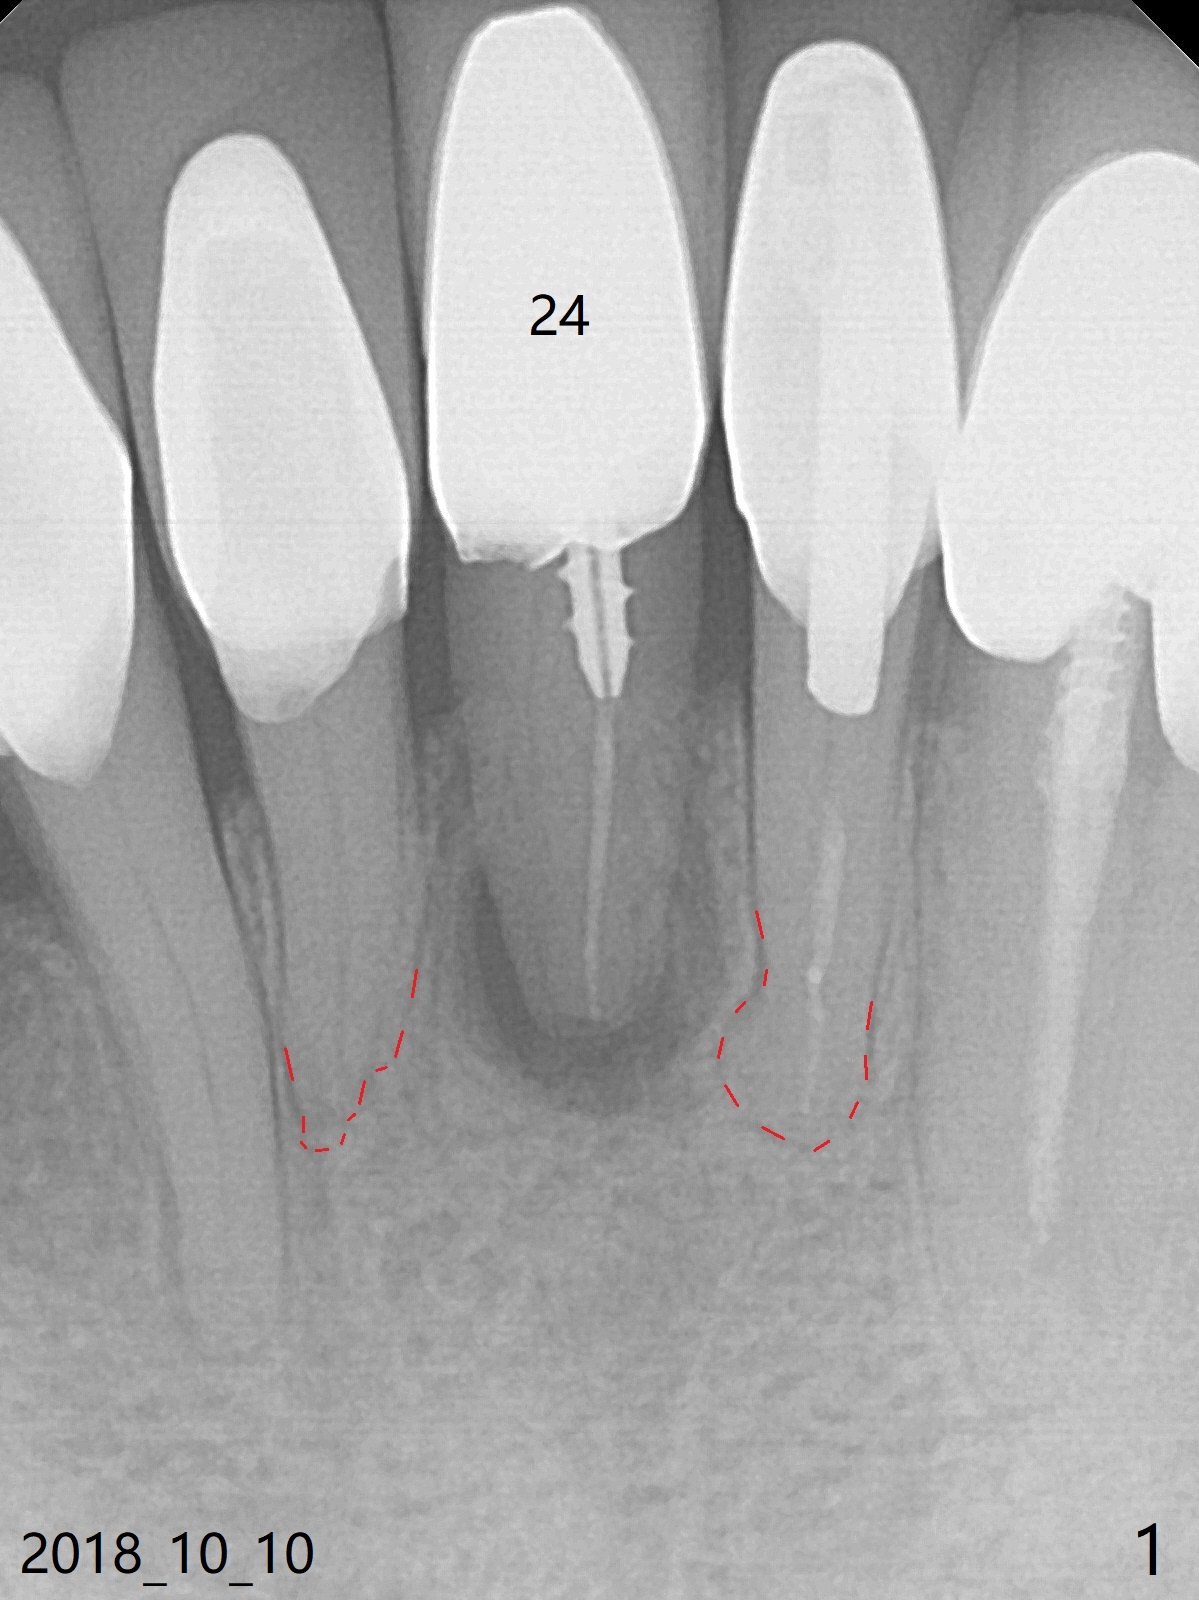

A 74-year-old man finally agrees to have the tooth #24 to be extracted for immediate implant with 3-year mobility and buccal shift (occlusal trauma or root fracture, Fig.0,1). Because of curved root tips of the neighboring teeth (Fig.1 red dashed line), the initial osteotomy will be created mesially (Fig.2 red arrow), followed by change in trajectory (Fig.3). The initial depth will be 14 mm (gingival level; ~ 12 mm bone level (easy change in trajectory and/or position). PA will be taken. The implant will be 2.5x14 mm (Fig.4).